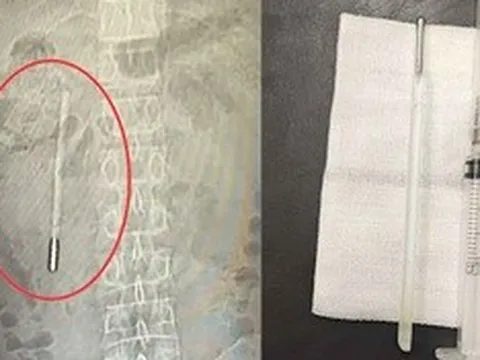

Ảnh minh họa.